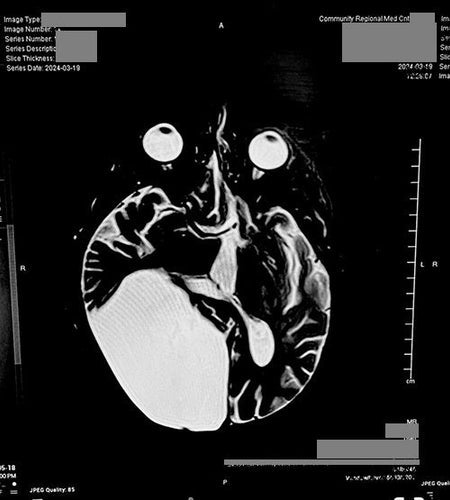

A Life-Changing Moment After a Brain Cyst Diagnosis

I wanted to take a moment to share my situation with you. Last March, just two days after my 59th birthday, I experienced my first-ever seizure. It was a major one that landed me in the hospital, and a CT...